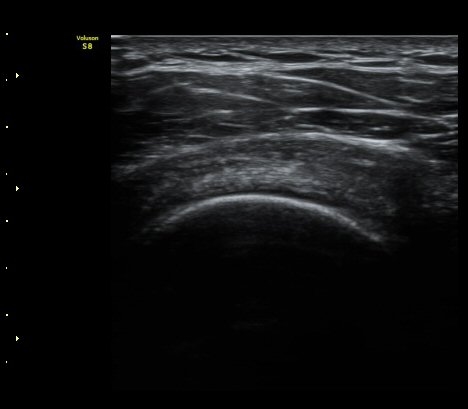

ÀÌµÎ¹Ú±Ù°Ç È¾´Ü¸é°Ë»ç¿¡¼­ ƯÀÌ ¼Ò°ß ¾øÀ½

(no specific abnormal findngs with transverse scan of biceps tendon) »çÁø 1, 2